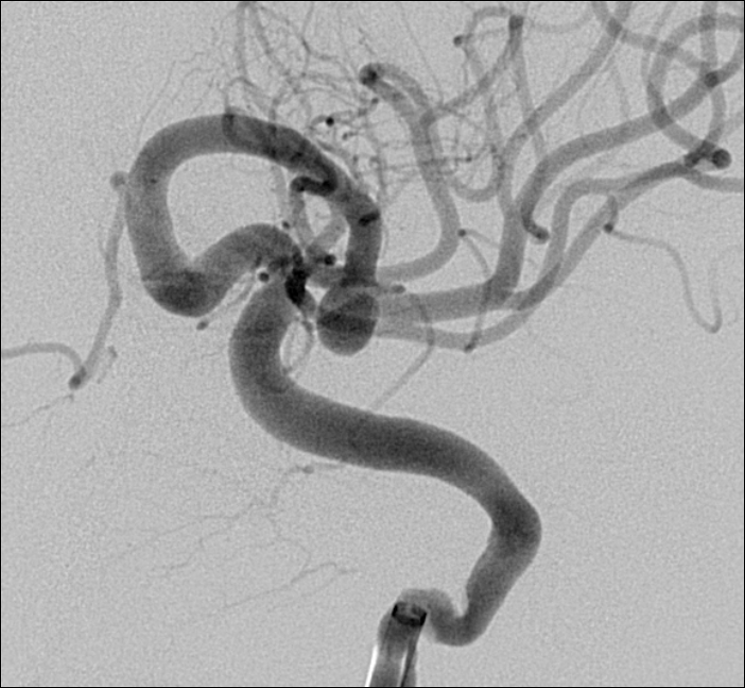

Mujer de 69 años con aneurisma incidental en la ACM.

Con un buen posicionamiento de los balones se logró el cierre completo del aneurisma con seguridad y control garantizando la permeabilidad de las ramas. En este caso no se completó el tratamiento con stent por que la paciente debe someterse a una cirugía reciente.